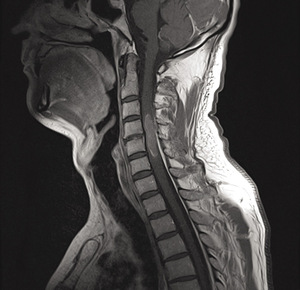

Podstawowym badaniem pozwalającym wykryć guza śródrdzeniowego jest obrazowanie rezonansem magnetycznym (MR) (ryc. 1, 2). Badanie to wykonywane jest w czasie T1 i T2 zależnym, bez podania środka kontrastowego i po jego zastosowaniu. Najbardziej przydatne jest obrazowanie w trzech projekcjach: strzałkowej, poprzecznej i czołowej.9